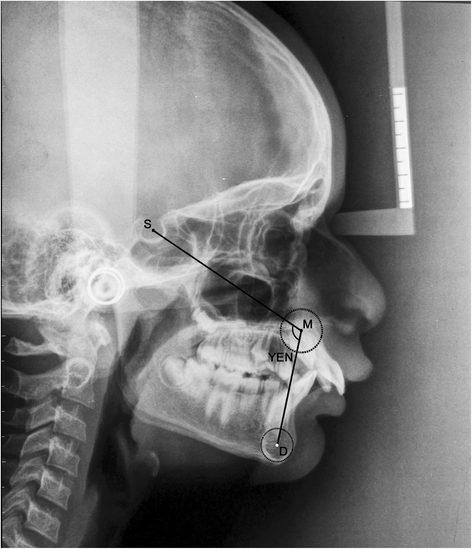

The pre-treatment and post-functional lateral cephalograms of 25 subjects (17 males, 8 females) with class II division 1 malocclusion treated with twin block functional appliance were selected. Five angular (ANB, β angle, APDI, YEN angle, W angle) and two linear (Wits analysis, App-Bpp) parameters were traced on both sets of cephalograms. Paired Student’s t-test, one-way ANOVA, post hoc test, and Karl Pearson correlation statistical analysis were performed.

All the parameters considered in our study showed highly significant difference in pre-treatment and post-functional values, suggesting their reliability (p < 0.0001). When ANB angle was compared with the other angular parameters, a highly significant change in the mean value of the difference in pre-treatment (T1) and post-functional (T2) values was noted (p < 0.001). No significant change was seen when comparing the mean value of the difference in T1 and T2 between linear parameters (p = 0.949).

The angular parameters used were as follows (Table 1):

According to Tables 4 and 5, it is suggested that either the YEN angle or W angle can be used to assess skeletal anteroposterior discrepancy (mean difference = −0.6, p = 0.982, r = 0.894). With reference to the YEN angle, jaw rotations due to growth and treatment can mask true skeletal dysplasia [25]. The YEN angle requires accurate tracing of the premaxilla for its assessment. The W angle also requires accurate tracing of the premaxilla and locating its center, which is difficult. Also, determining which of the jaws is prognathic or retrognathic is difficult [12]. Thus, when accurate tracing of the premaxilla for the assessment of the W angle and YEN angle is not possible, the β angle can be used as it shows least correlation with the YEN angle and W angle (Tables 4 and 5).